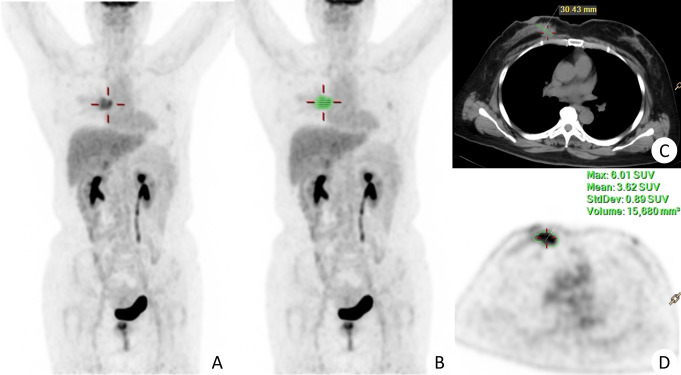

Methods: In total, 114 patients with BC performed 18F-FDG PET/CT scans. Patients were randomly assigned to a training set (n = 79, 55 cases of Ki67 + and 24 cases of Ki67-) and a validation set (n = 35, 24 cases of Ki67 + and 11 cases of Ki67-). Thirteen clinical characteristics and 704 radiomics features were extracted, and 4 clinical and 8 radiomics features were selected. Three models were developed, including the clinical model, the radiomics model, and the combined model. Model performance was evaluated using the ROC curve, and clinical utility was assessed through decision curve analysis (DCA).

Results: The N stage, tumor morphology, SUVmax, and the longest diameter significantly differed between Ki67 + and Ki67- groups (all P < 0.05). Eight radiomics features were selected for the radiomics model. The area under the curve of the combined model in the training and test group was 0.90 (95% CI: 0.82∼0.97) and 0.81 (95% CI: 0.64∼0.99), respectively. The combined model significantly outperformed both the radiomics model and the clinical model alone (P < 0.05). The DCA curve demonstrated the superior clinical utility of the combined model compared to the clinical model and radiomics model.

Conclusions: PET/CT image-based radiomics features combined with clinical features have the potential to predict Ki67 expression in BC.